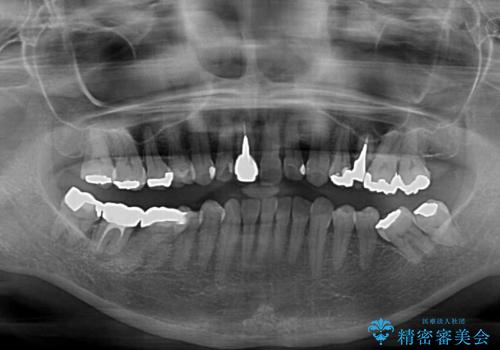

- 上下前歯のデコボコと、治療途中の歯を気にして来院された患者様です。

ご家族がインビザラインにて矯正治療を行っていたため、ご本人の希望によりインビザラインによるマウスピース矯正を行うこととしました。

根管治療が必要な歯は事前に処置を行った上で矯正治療を開始し、概ね歯列が整ったところでセラミッククラウンなどに置き換え、その後インビザラインを1セット使用して仕上げていくこととしました。